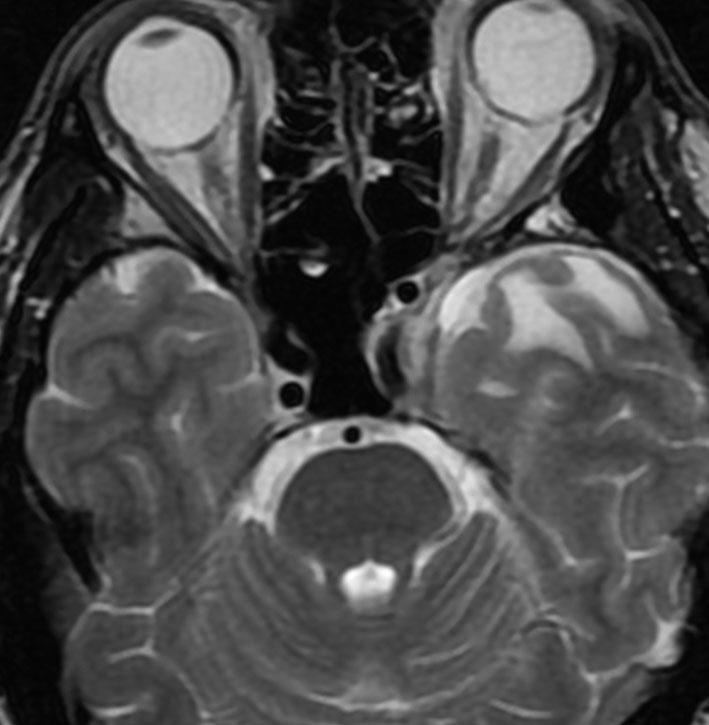

小脳類皮のう胞

偶然発見された女の子のものです。左のCTで石灰化があります。右の拡散強調画像 DWI で白く高信号に描出されるのが特徴です。手術では腫瘍内部に毛髪がたくさんありました。後下小脳動脈に強く癒着していて,脳軟膜からの剥離もできませんでしたが,完全摘出しました。無症状でも”完全”摘出 complete removal するべきです。